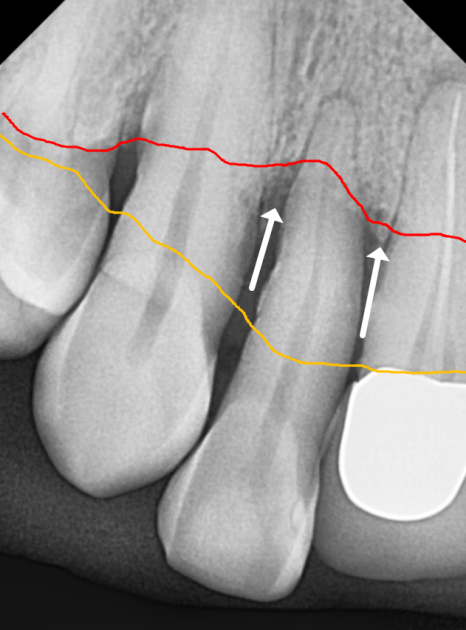

환자분께서 중앙 앞니(#11)가

잇몸이 부었다가 가라앉기를 반복한다며

다시 내원하셨어요.

251125

자세히 살펴보니 고름이 빠져나온 흔적이 보이네요.

흔들림도 이전보다 심해진 상태였습니다.

C뿌리 끝 염증도 더 심해진 상황...

안타깝지만 이 치아도 발치 후

임플란트로 재건하기로 결정했습니다.